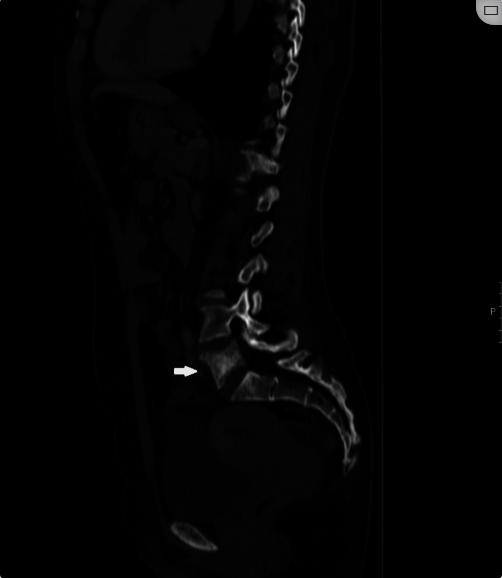

图1、腰椎CT扫描,矢状面

腰椎CT显示病变涉及身体,左椎弓根和L5椎骨的左上关节面